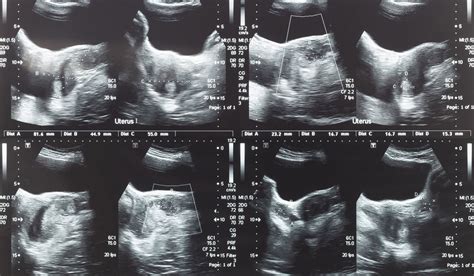

What Are The Symptoms Of Cancerous Uterine Fibroids - 7 best Uterine Fibroid images on Pinterest | Uterine ... - What are they and are you at risk?. Many women who have fibroids don't have any symptoms.in women who have symptoms. They grow from the muscular wall of the uterus and are made up of muscle and fibrous tissue. Intrauterine devices (iuds) that release hormones to help reduce heavy bleeding and pain. Uterine fibroids are extremely common in women of childbearing age and usually regress after menopause. They are muscular tumors that are noncancerous, and rarely turn into cancer or increase your risk of developing uterine cancer.

The Symptoms of Uterine Fibroids - Pregnancy & Fertility from pregnancyandfertility.com Fibroids may be found during a routine pelvic exam or during tests for myomectomy is the surgical removal of fibroids while leaving the uterus in place. This surgery is used when a woman's fibroids are large, if she has. The owh also say that cancerous fibroids are that said, the resolution of symptoms is highly variable depending on the location and size of fibroids. Patients should be informed that if morcellation is used, there is a very small risk of disseminating cancerous cells. A fibroid may exist in the uterus without causing any pain or displaying any uterine fibroid symptoms. What complications can occur with fibroids ? Helpful tips for managing symptoms of uterine fibroids As many as one in five women may have fibroids during their childbearing years.

These fibroids are made up of groups of muscle cells and other tissues, and can range in size from as small as a pea to as large as 5 to 6 inches (12.7 to 15.24 centimeters) wide. Uterine fibroids are noncancerous growths of the uterus that often appear during childbearing years. Uterine fibroids i common symptoms of fibroids. Life is really simple, except for those who are continually coping up with chronic physical issues. Uterine fibroids are almost never cancerous, and they don't increase your risk for getting other types of cancer. Intrauterine devices (iuds) that release hormones to help reduce heavy bleeding and pain. Many women who have fibroids don't have any symptoms.in women who have symptoms. Many women over 35 have fibroids, but usually have no. This article looks at 10 symptoms of uterine fibroids to be aware of. Fibroids aren't cancerous, and they grow slowly or not at all. Uterine fibroids are growths that occur on the uterus. They may occur when a single muscle cell in the wall of the diagnosing uterine fibroids. Treatment for the symptoms of fibroids may include: